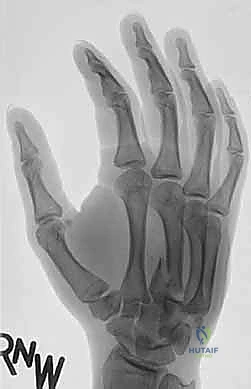

يُعتبر التشخيص الدقيق هو حجر الزاوية في نجاح العلاج. المشكلة الكبرى في كسور وخلع مفصل الكربوميتاكاربال هي أن التراكب التشريحي لعظام الرسغ والمشط في صور الأشعة السينية الأمامية الخلفية (AP View) العادية يجعل من الصعب جداً رؤية الخلع.

- صور الأشعة السينية المتخصصة (X-Rays): لا يكتفي الدكتور بالصور التقليدية، بل يطلب وضعيات تصوير خاصة (مثل الوضعية المائلة Oblique View بـ 30 درجة) التي تظهر قاعدة المشط بوضوح وتكشف الخلع الخفي.